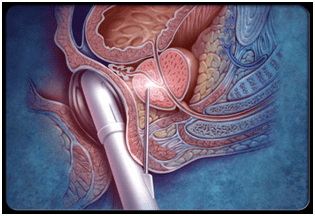

Physical examination OR Digital rectal examination: The Urologist gently feels the consistency of the prostate using a well lubricated gloved finger through the anus.

Once there is a strong suspicious on DRE and psa testing that a man may have prostate cancer one must proceed to confirm the diagnosis by Biopsy testing.